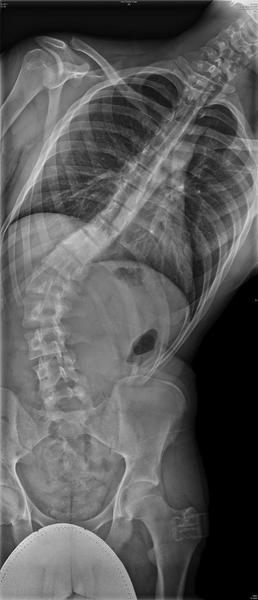

Hey guys, I don't post much here that much, some of you may not remember me or even know me. I have been very busy for the past few months with school and with my back. I have been dealing with scoliosis for over a year and a half now. And It turns out I first caught it after my growth spurt when I was 18. I had an x-ray and it was "supposedly" 15 degrees by stupid doctor number 1. It wasn't actually 15 degrees, it was 40 degrees and by 09, it had gone to 53*. Now my only option is a spinal fusion. It's really a big problem for me, it causes daily pain. I am having surgery Monday, December 28, 2009. I would just really like it if you guys wished me luck and kept me in your prayers so I have a safe surgery and have no problems. Thanks.

Here are some X-rays to show you how my spine looks.